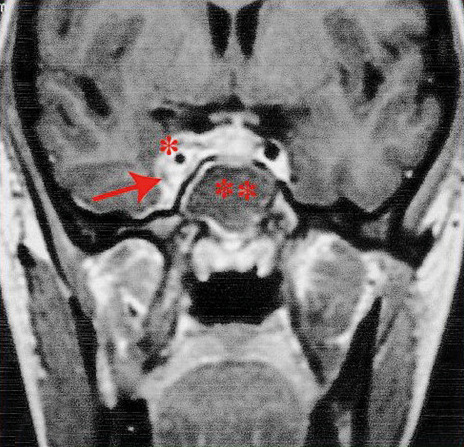

Plus rarement, il peut s’agir d’une thrombose du sinus caverneux (fig. 4) – notamment sur cellulite de la face, avec œdèmes palpébraux, céphalées et fièvre.